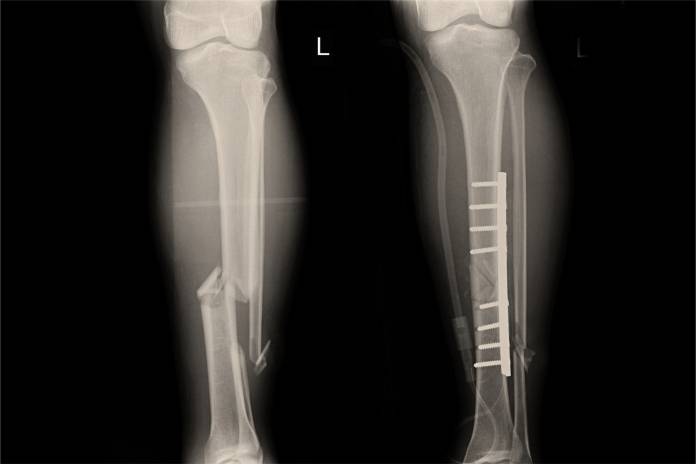

Vor allem Brüche, deren Knochenfragmente gegeneinander verlagert (disloziert) sind oder die sogar offen sind (der Knochen durchstößt die Haut), werden operativ behandelt. Außerdem kommt die Operation z. B. dann in Frage, wenn der Knochen trotz langer Ruhigstellung nicht richtig zusammenheilt. Die Operation kann in Vollnarkose durchgeführt werden, teils auch in Regionalanästhesie, also in Betäubung eines ganzen Körperteils.

In einer Operation werden die Anteile des gebrochenen Knochens reponiert (wieder in die richtige Lage gebracht). Dann müssen sie mit Metallstrukturen aneinander befestigt werden (Osteosynthese). Diese Osteosynthese-Materialien können je nach der Bruchart Nägel im Markraum (Marknägel), Schrauben und Platten oder ein äußeres Gestell (Fixateur externe) sein. Umgebende Verletzungen wie Bänder-, Sehnen-, Muskelverletzungen werden ebenfalls versorgt sowie gegebenenfalls geschädigte Gefäße und Nerven.

Der Marknagel ist ein häufig genutztes Mittel in der operativen Behandlung von Unterschenkelbrüchen. Quere und schräge Schaftbrüche können gut mit einem Marknagel behandelt werden. Meist vom Schienbeinkopf aus, der zunächst angebohrt wird, wird der Marknagel in den Knochenmarkraum des Knochens eingeführt. Manchmal ist es vorteilhaft, den Marknagel ohne Bohrung einzuführen und ihn stattdessen hineinzuschlagen. Der Marknagel kann bei komplizierten Brüchen (Trümmerfrakturen, Verdrehungsfrakturen, Brüchen im Gelenkbereich) auch mit Querbolzen versehen werden. Dies nennt sich Verriegelungsnagel.

Unter einigen Voraussetzungen ist es besser, den Schienbeinbruch mit Schrauben und Platten zu versorgen. Das kann beispielsweise bei Gelenkbrüchen oder bei nicht für einen Marknagel geeignetem Knochenmarkraum der Fall sein.